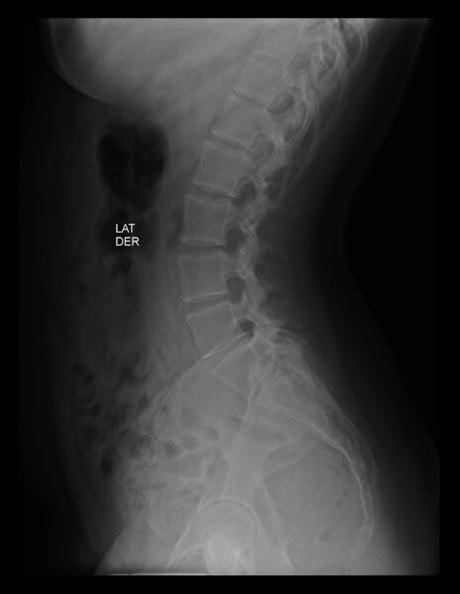

RADIOGRAFIA AP Y LATERALES DE COLUMNA LUMBAR

HALLAZGOS:

-Tejidos blandos, con densidad y morfología respetada, sin evidencia de lesiones.

-Columna vertebral, central. Sin listesis. Lordosis lumbar, con aumentos angulación.

-Cuerpos vertebrales con altura preservada, sin evidencia de lesiones líticas, blásticas o perdida de la contigüidad.

-Plataformas vertebrales, con adecuada densidad y morfología.

-Pedículos, laminas posteriores sin evidencias de lesiones líticas, blásticas o perdidas de la contigüidad.

-Apófisis transversas de L5, con fusión de apófisis derecha con sacro, y apófisis transversa izquierda con longitud mayor a 19 mm. Resto de apófisis espinosas, transversas y facetas sin evidencias de lesiones líticas, blásticas o perdidas de la contigüidad.

-Espacio intervertebrales, con adecuada amplitud.

-Neuro forámenes, con diminución de su amplitud en L5-S1, resto con adecuada amplitud.

OPINIÓN RADIOLÓGICA:

EL PRESENTE ESTUDIO RADIOGRAFICO, CON HIPERLORDOSIS LUMBAR.

SACRALIZACIÓN DE L5 CASTELLVI TIPO IV.

APARENTE ESTENOSIS DE NEURO FORÁMENES DE L5-S1.

CORRELACIONAR CON DATOS E HISTORIA CLINICA DEL PACIENTE.